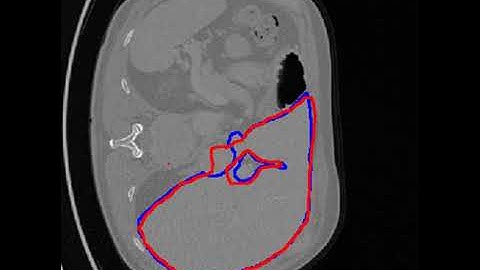

Detection of Tumor in Liver Using Image Segmentation and Registration Technique